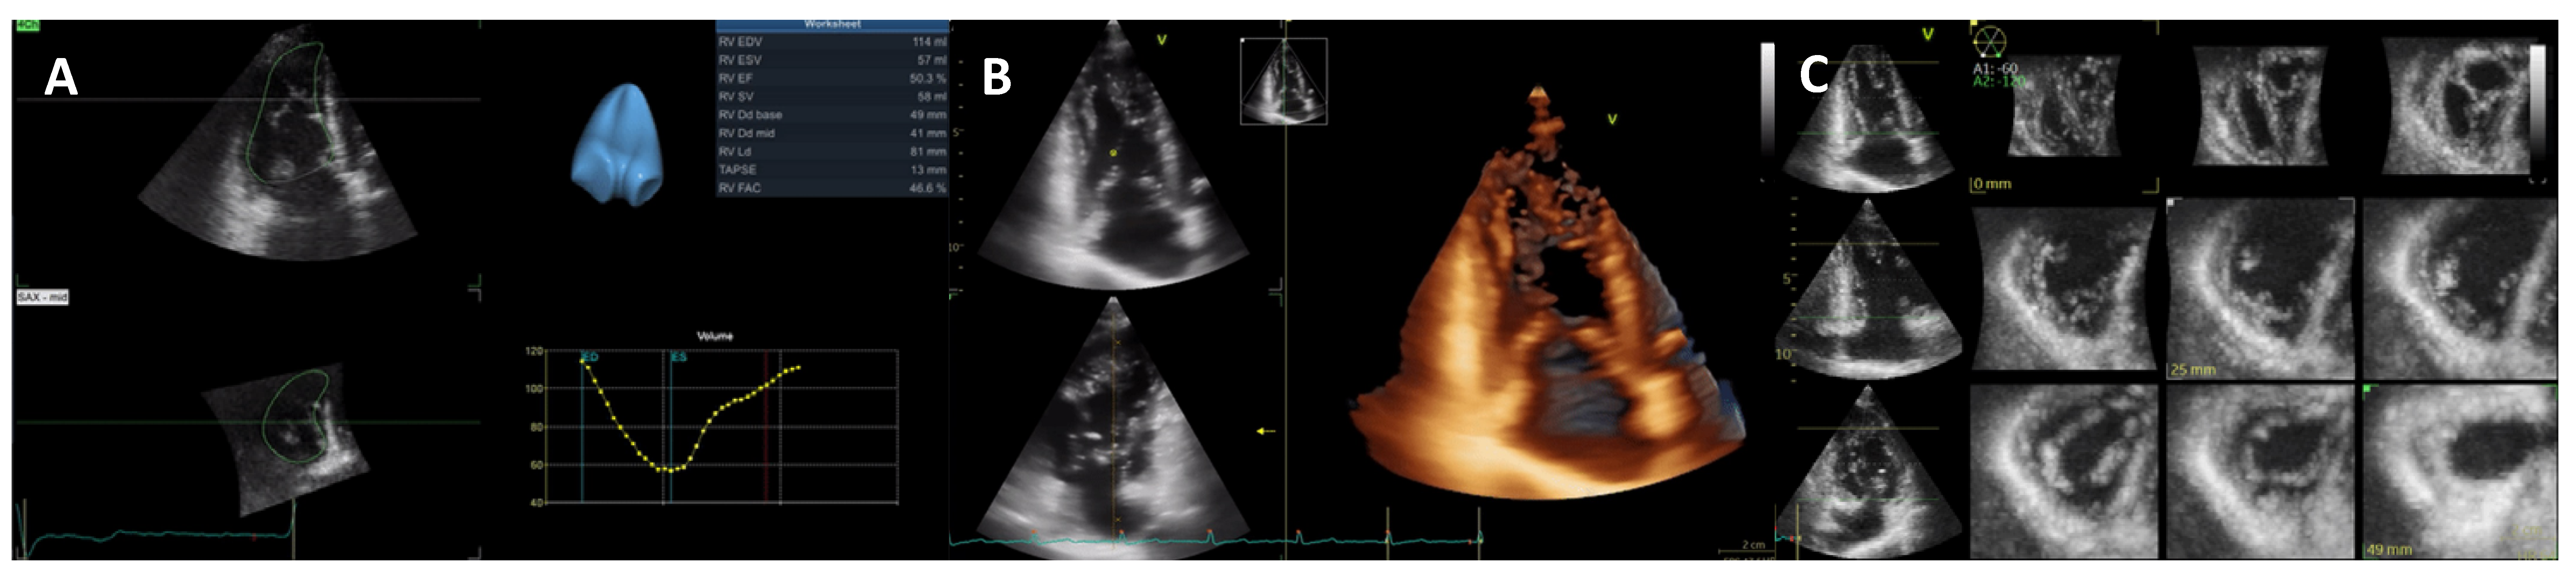

3. Dilated Cardiomyopathy